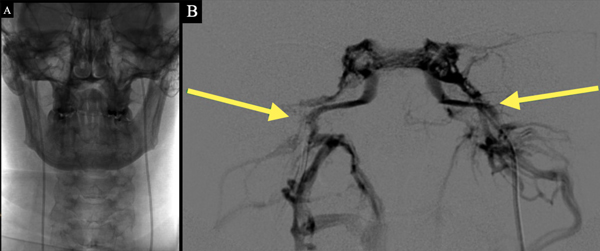

4. CSPI: en casos de RM negativa para tumor hipofisario o con imagen < 6 mm (hasta el 10 % de la población general puede presentar imágenes hipofisarias incidentales de menos de 5 mm22). Se realiza dosaje de ACTH y prolactina en sangre periférica y en ambos senos petrosos inferiores en condiciones basales y luego del estímulo con hormona antidiurética. Se considera significativo un gradiente central/periférico > 2 en condiciones basales o > 3 tras el estímulo. Un gradiente intersinusal ≥ 1,4 sugiere lateralización del tumor23-25. (Figura 2)

Figura 2. Cateterismo de senos potrosos inferiores. A. Imagen radiológica sin sustracción donde se visualizan ambos catéteres en posición simultáneamente. B. Imagen con sustracción donde se constata correcto posicionamiento de catéteres y tinción de ambos senos petrosos inferiores.